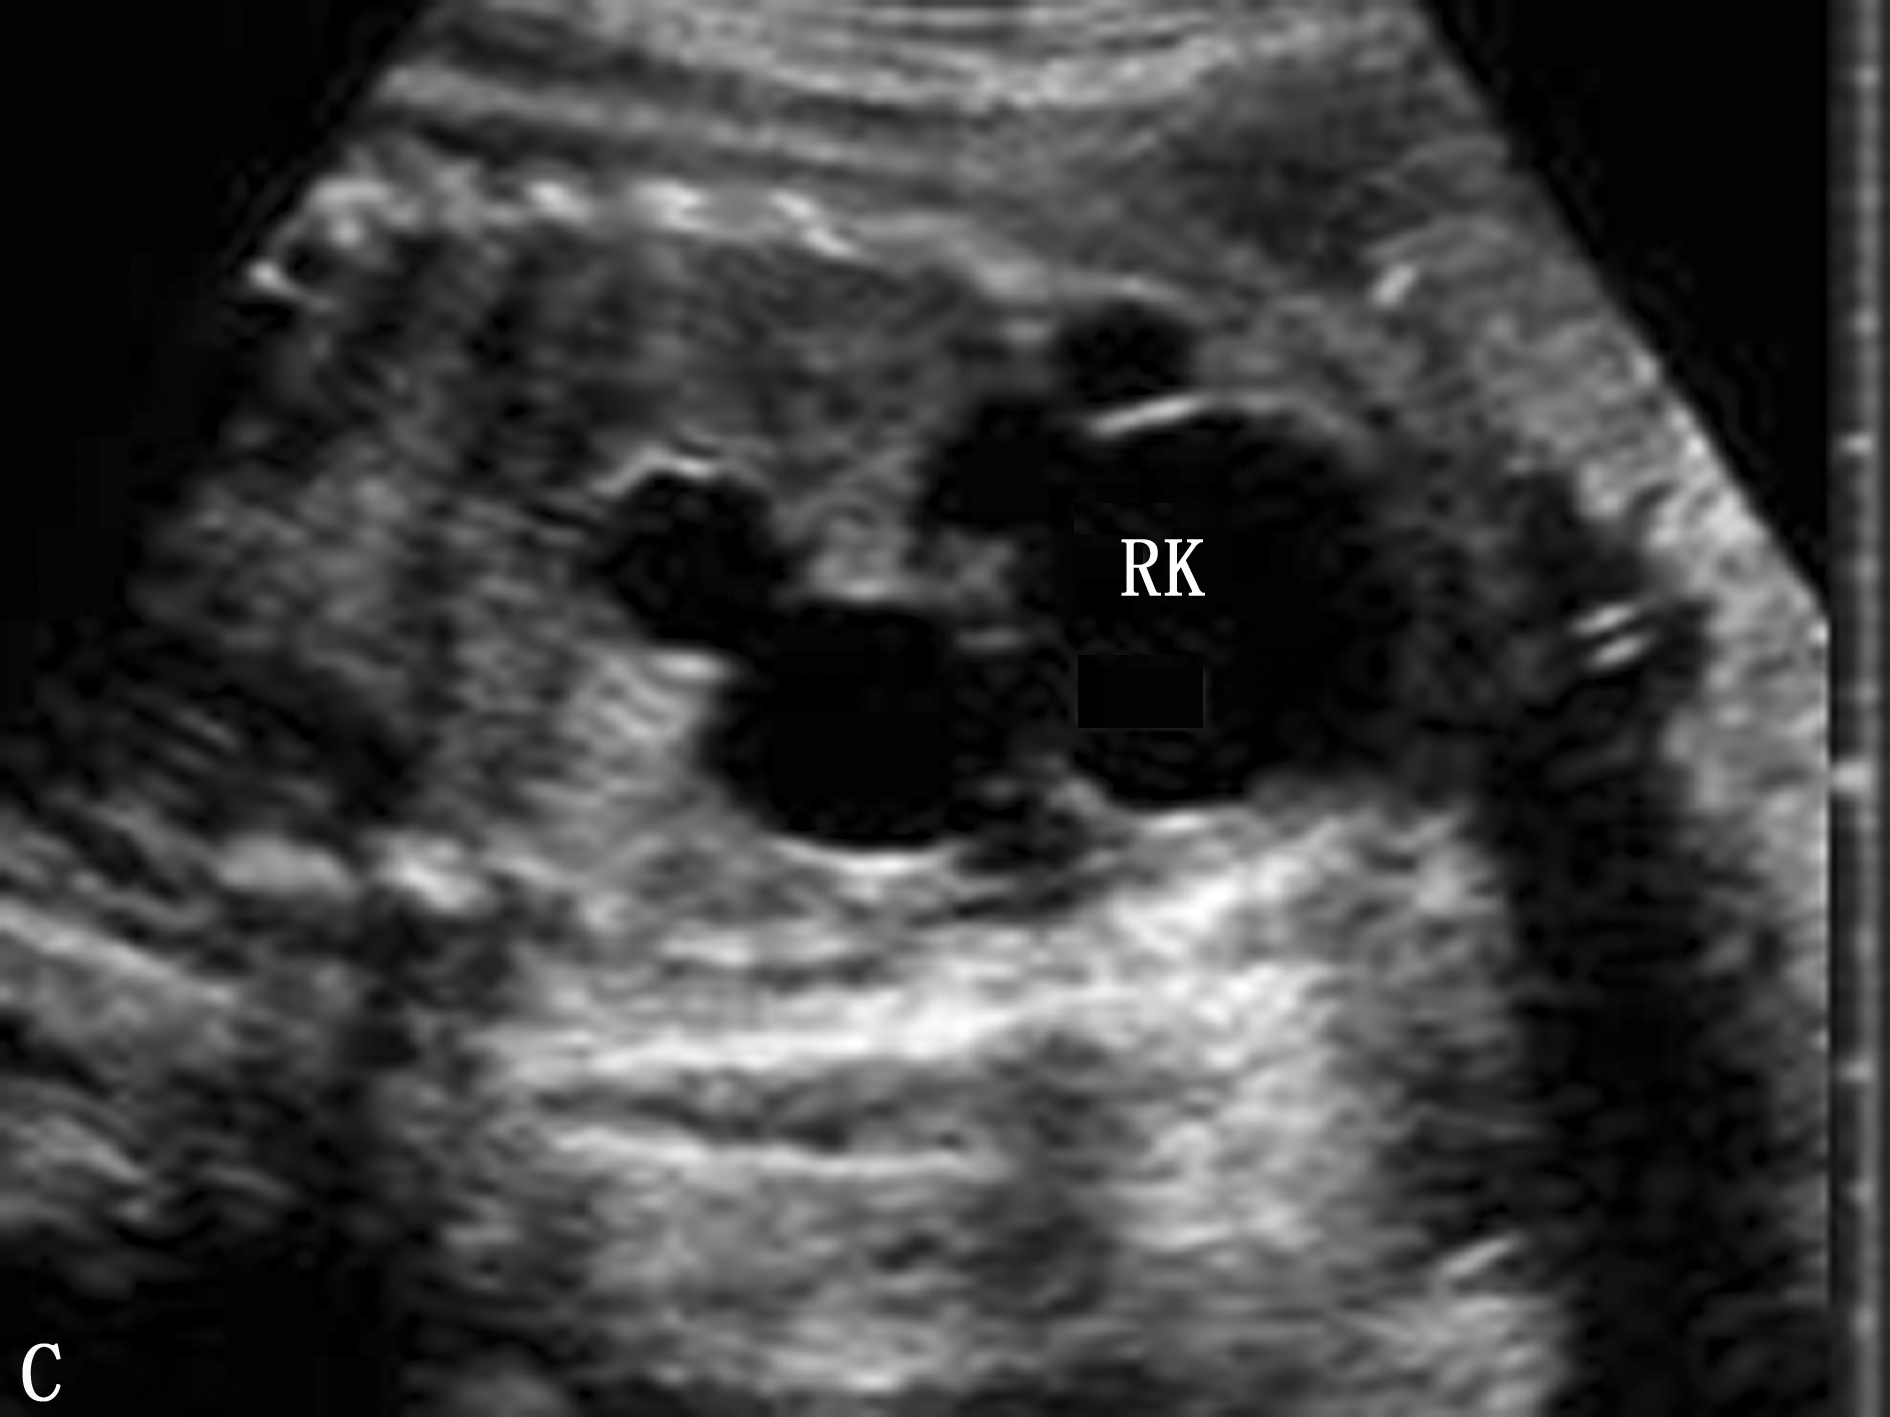

图2:上AB图同一胎儿34周复查右侧肾积水明显加重